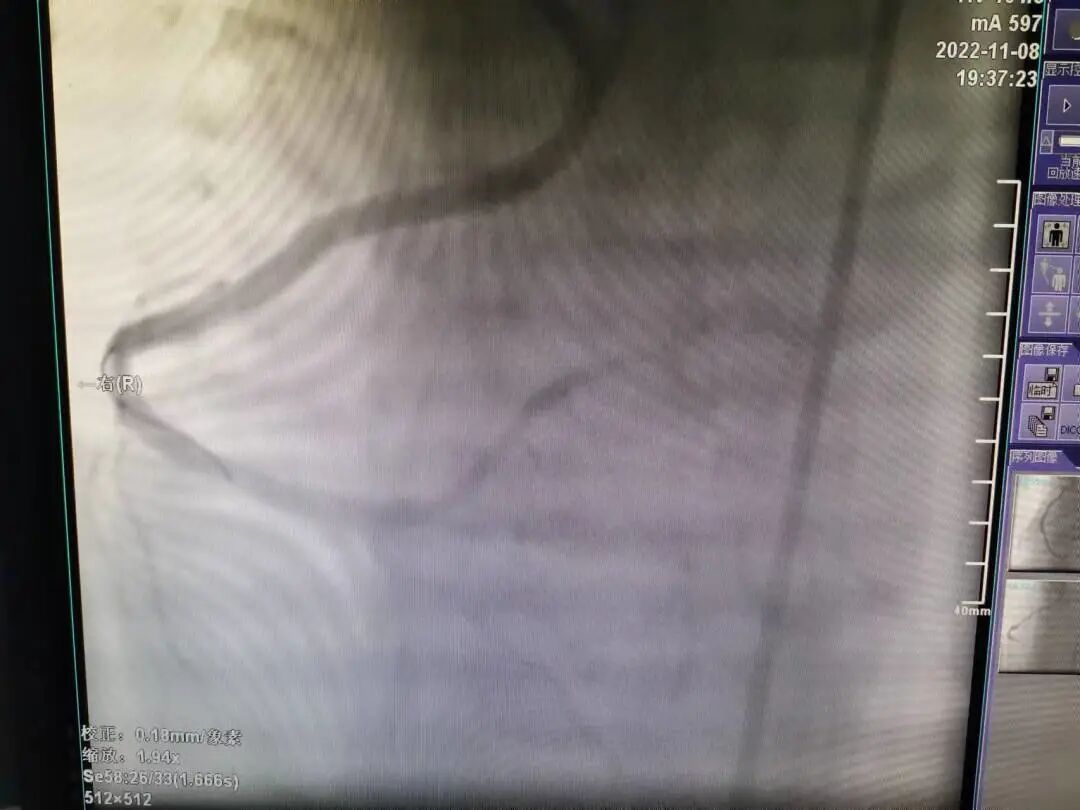

118日,在介入室的配合下,由郑涛副主任医师主刀,郭英普主治医师和封挺约主治医师为助手,为患者开展冠脉介入手术。术中选择了右侧股动脉路径,尝试多次后JR造影管终于找到右冠脉开口,造影显示右冠开口在升主动脉后壁并高于左冠开口,为极少见的冠脉变异开口,同时造影显示右冠近段以远完全闭塞,前向血流TIMI 0级。

右冠脉造影显示右冠开口变异伴右冠完全闭塞